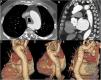

A 73-year-old male patient presented to the emergency department with a chief complaint of central chest pain for the previous three days. His medical history revealed heavy smoking, hypertension and atrial fibrillation (AF). His physical examination, ECG, chest radiograph and laboratory tests were unremarkable (AF at 70-80 bpm). Due to lack of response to conservative drug treatment, an aortic computed tomography angiography (CTA) scan was performed, which detected a bulge with a ‘mushroom cap’ appearance in the posterior wall of an aberrant right subclavian artery (ARSA), reported as limited dissection (Figure 1 and Supplementary Videos A and B). After multidisciplinary committee assessment, it was decided to perform endovascular repair. A Gore endoprosthesis in a nitinol-covered stent was anchored at the origin of the left subclavian artery and an Amplatzer Vascular Plug was used to exclude the dissection of the ARSA from circulation. Initially, the patient evolved favorably but a few days later he presented an acute recurrence of chest pain. A new CTA showed signs of type III endoleak (Supplementary Video C), and emergent endovascular repair was planned. Unfortunately, after anesthetic induction, the patient presented severe hypotension with hemodynamic instability that quickly evolved to cardiogenic shock, multiorgan failure and, eventually, death.

Computed tomography angiography of the aorta, axial view (A), multiplanar reformatting in sagittal view (B), and volume rendering in oblique posterior views (C-E). Focal bulging of 21 mm×8 mm with a ‘mushroom cap’ appearance at a Kommerell diverticulum of the aberrant right subclavian artery (yellow arrows in A and B, black arrows in C-E). The latter compresses the esophagus posteriorly along its course to the right and passes 8 mm posterior to the right posterolateral margin of the trachea. The aortic size is within normal range and no other structural abnormalities of the aorta are observed. Note that vascular repair at this location may entail technical difficulties, particularly anchoring the endoprosthesis at the origin of the right subclavian artery. In addition, total exclusion of the dissected segment cannot always be achieved.

Limited or subtle dissection is an uncommon form of acute aortic syndrome (AAS), and only a few case series have been published in the literature. Echocardiography and particularly CTA with cardiac gating can be considered the imaging modalities of choice because of their availability, speed and precision. The CTA appearance of limited dissection consists of an outward bulging oval or band-like luminal contour defect, resembling a mushroom cap. In the presence of these signs, emergent treatment is recommended, similarly to other types of AAS. Of note, Kommerell diverticulum has an increased risk of dissection and endovascular repair is a potential therapeutic strategy in limited dissections in this location, enabling the affected segment to be excluded. In this case, endovascular therapy was preferred over surgical treatment due to the patient's physical condition and the dissection type and location.